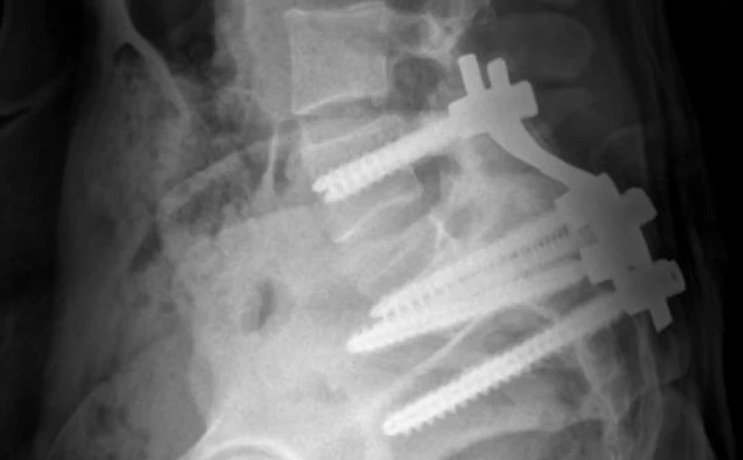

척추 전방전위증은 척추의 특정 마디가 제자리에서 앞으로 밀려나면서 신경을 압박하는 질환입니다. 주로 요추 4번과 5번 사이에서 자주 발생하며, 심한 경우에는 허리 통증뿐 아니라 다리 저림, 감각 이상, 보행 불편 등의 신경 증상이 동반될 수 있습니다.

척추는 여러 개의 뼈(척추체)와 디스크, 인대, 근육이 정교하게 맞물려 안정성을 유지하는데, 이 중 하나라도 약해지면 구조적 불균형이 생기게 됩니다. 척추 전방전위증은 이 균형이 무너진 대표적인 예로, 척추를 잡아주는 심부근육이 약화된 상태에서 자주 나타납니다.

척추 전방전위증의 진행이 심하면 척추관이 좁아지면서 좌골신경통 같은 신경성 통증이 동반되기도 합니다. 이는 단순히 허리 근육 문제를 넘어선 신경적 불편함으로 이어질 수 있어 조기 관리가 중요합니다.